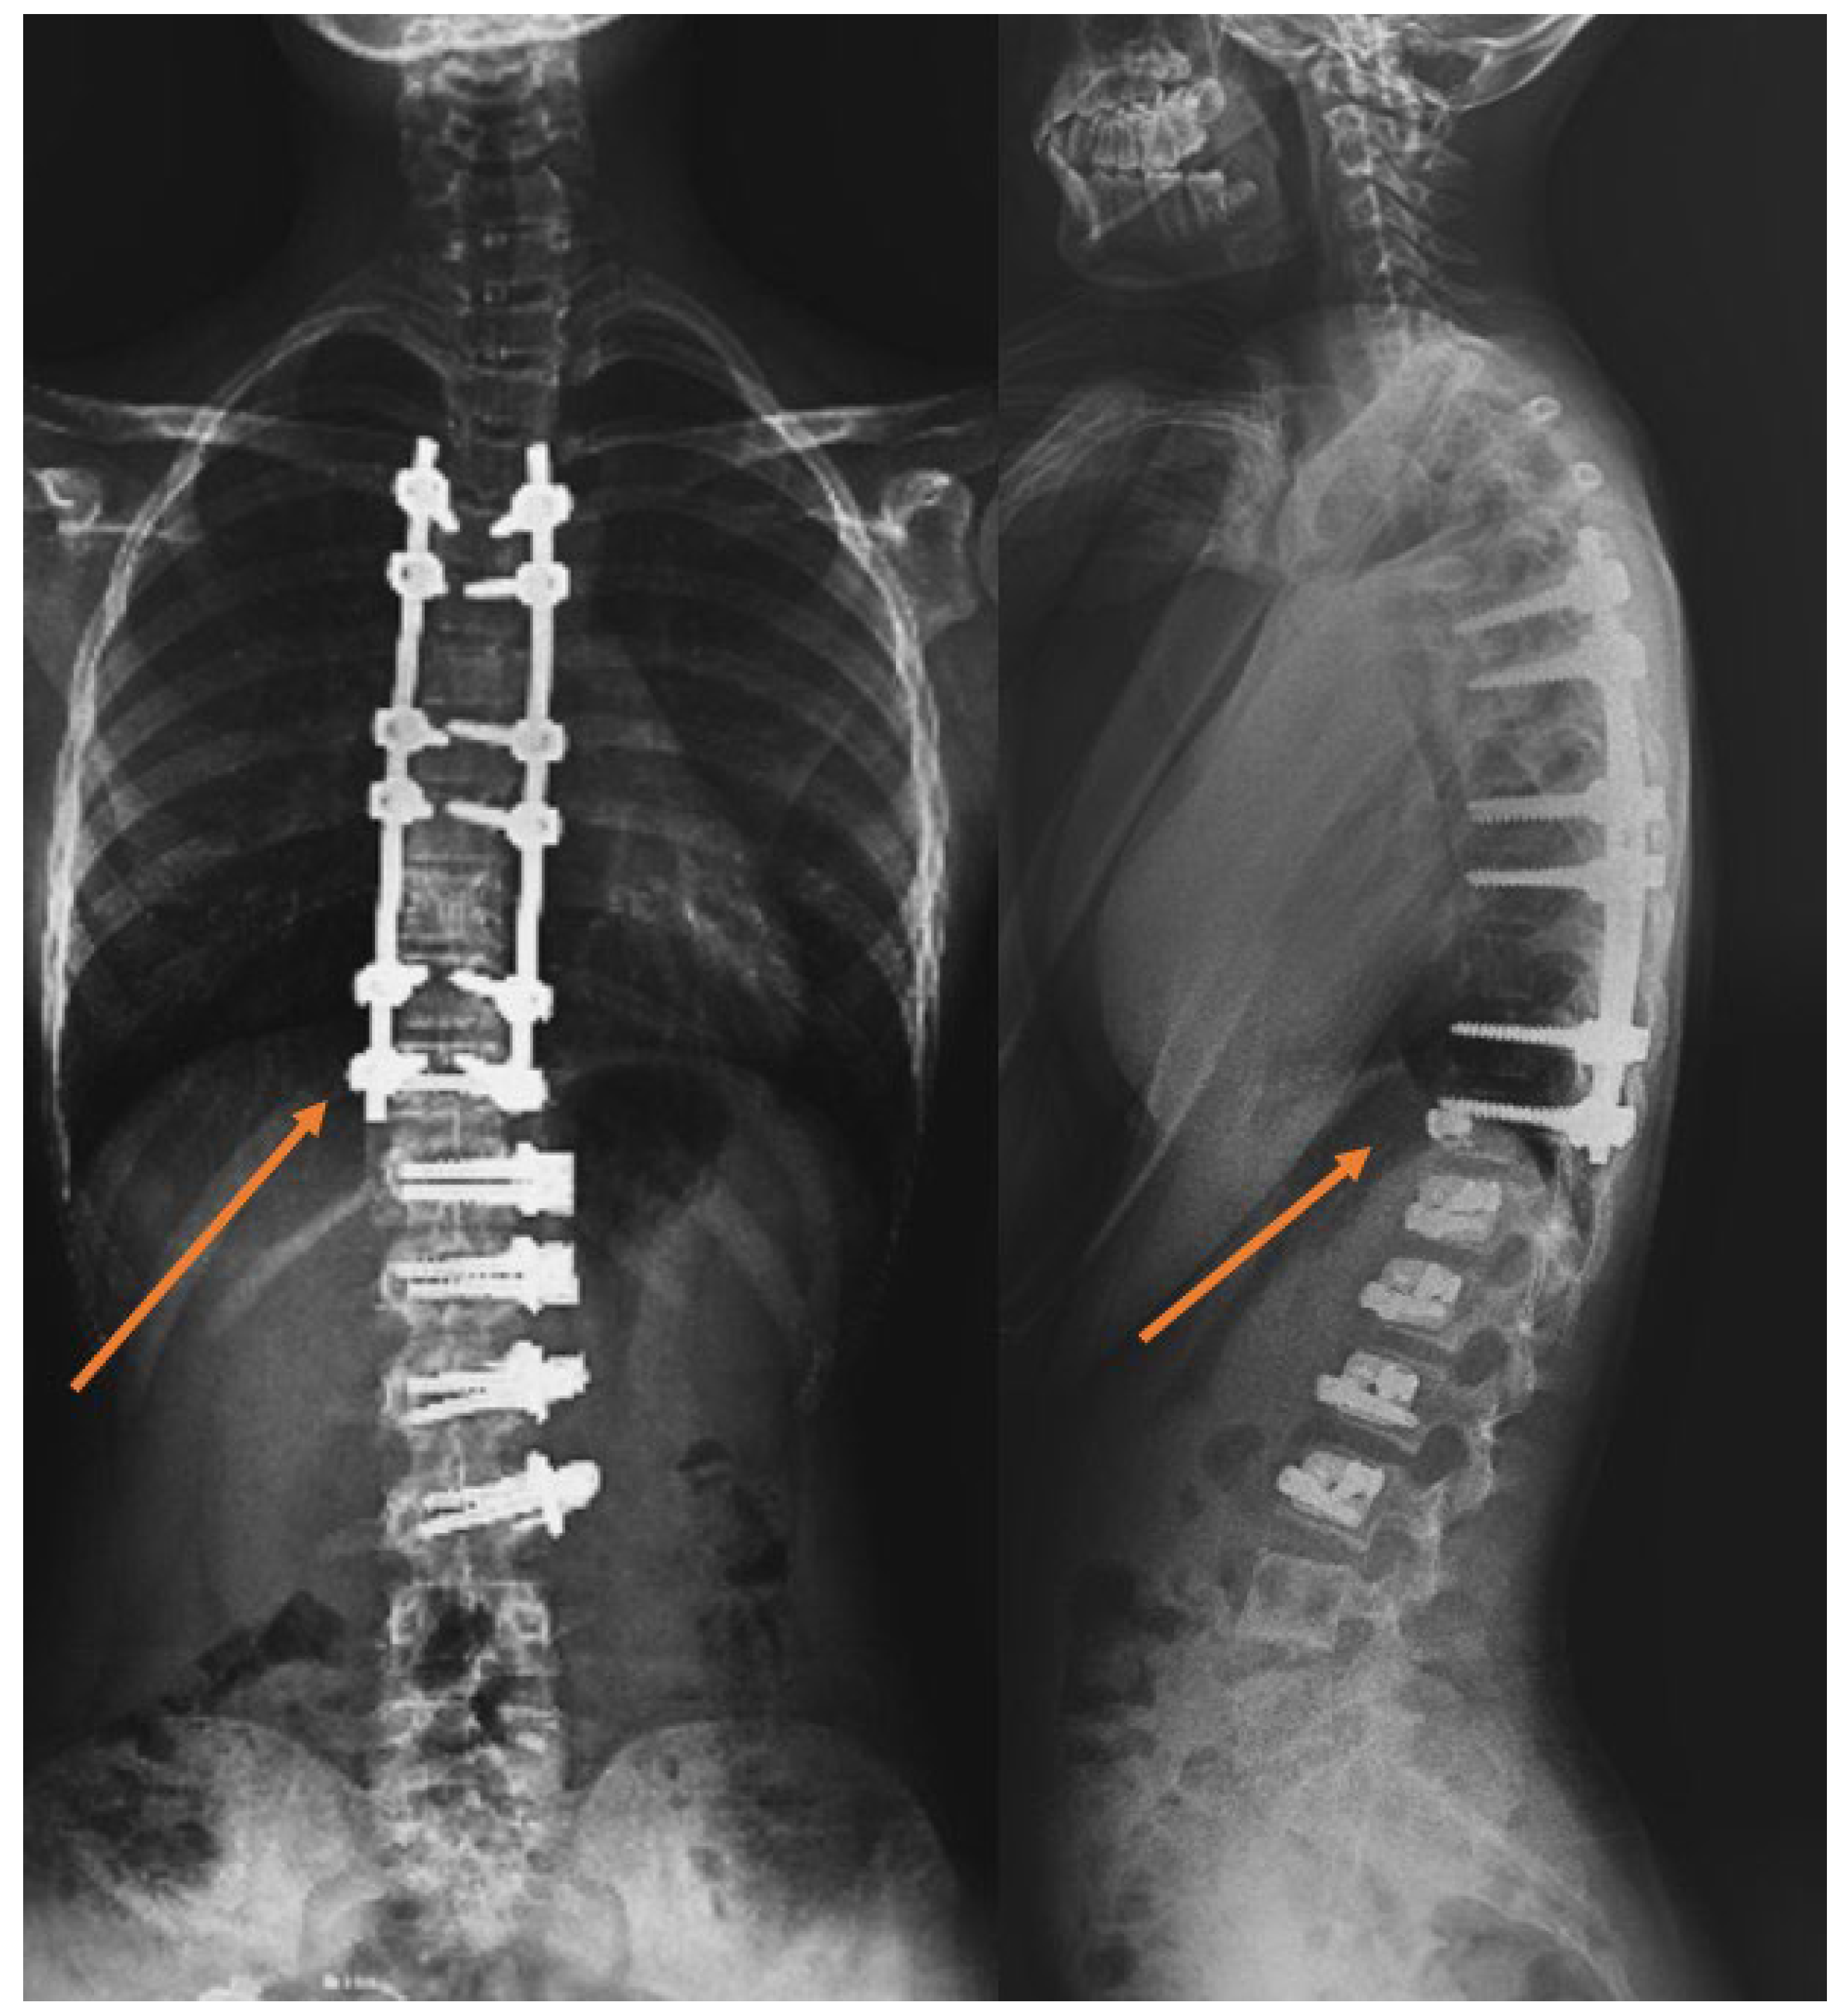

- In patients who underwent tethering, those with an LIV level at L2, L3, and L4 formed the thoracolumbar/lumbar AVBT group (Group 1). Patients who underwent AVBT in the thoracolumbar region and hybrid surgery, combining AVBT with thoracic fusion, were included in the AVBT group (Figure 1). The majority of thoracolumbar/lumbar AVBT cases underwent hybrid fusion procedures (9 out of 17, 52.9%).